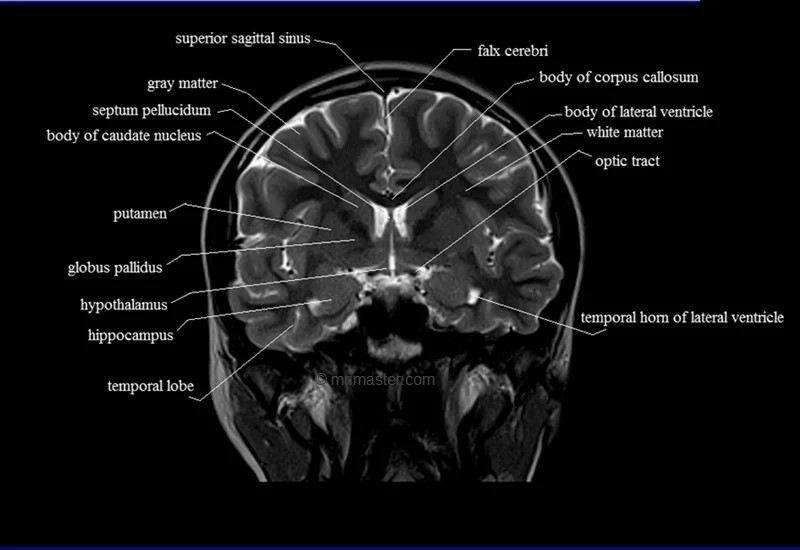

MRI Coronal Cross Sectional Anatomy of Brain

This MRI brain cross-sectional anatomy tool is absolutely free to use. Use the mouse scroll wheel to move the images up and down, or alternatively, use the tiny arrows (→) on both sides of the image to navigate through the images.